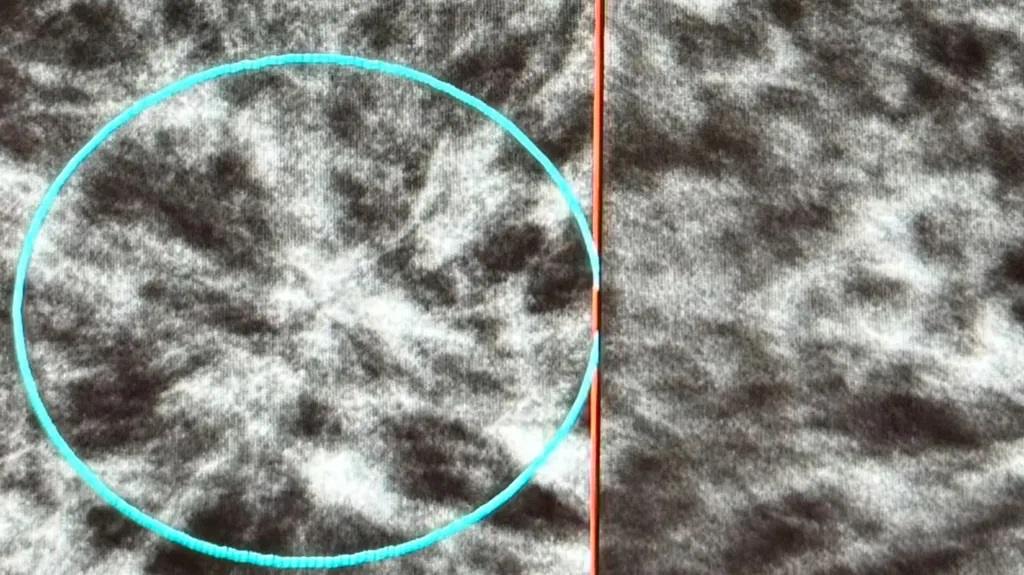

Το πρόβλημα με τον πυκνό ιστό είναι ότι εμφανίζεται λευκός στις κλασικές μαστογραφίες, όπως και οι όγκοι, γεγονός που δυσκολεύει τον εντοπισμό τους.

«Όταν το στήθος είναι πολύ πυκνό, είναι σαν να προσπαθείς να βρεις ένα λευκό σύννεφο μέσα σε έναν συννεφιασμένο ουρανό», είπε χαρακτηριστικά περιγράφοντας τη δυσκολία εντοπισμού καρκίνου.

Όγκοι όπως αυτός που έχει κυκλωθεί, αριστερά, εντοπίζονται δύσκολα σε πυκνούς μαστούς (Πηγή: BBC)